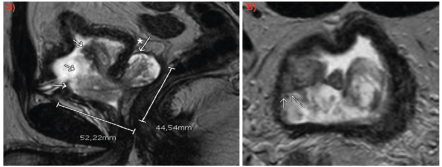

Pelvic magnetic resonance imaging (MRI) demonstrated a large prostatic tumour measuring 45 × 52 × 46 mm, extending from the left seminal vesicle into the bladder lumen (Figure 1). Flexible cystoscopy confirmed intravesical tumour extension without the involvement of the bladder trigone.

Figure 1. MRI (a): Sagittal slice: arrows indicating intravesical growth of the lesion. The asterisk with the arrow marks the involvement of the left seminal vesicle. (b): Axial slice: arrows indicating tumour contact with bladder wall.